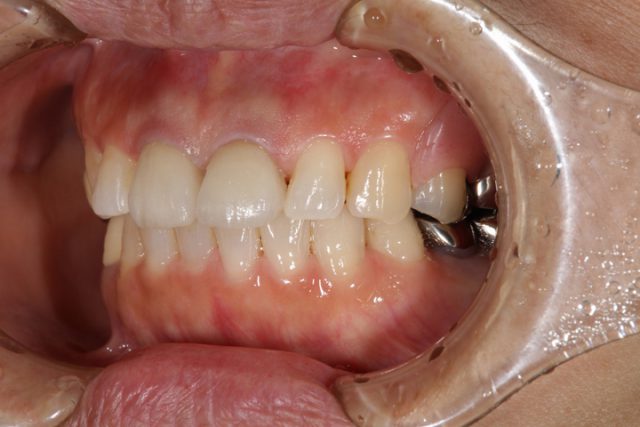

施術後

術後の画像です。前歯の隙間もしっかりと無くなり解消されています。周りの歯との色も自然です。被せ物の付け根はどうですか?被せ物だとはほとんど分からなくなっています。歯の裏面もオールセラミックによる施術では白くなりますのでほとんど被せ物だということは分からなくなります。

見た目も非常に美しくなり、食事後の歯のつまりもほとんど気にならなくなったと非常に喜んでおられました。